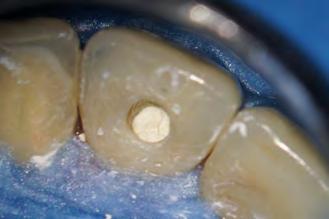

Caso clínico

Paciente del género femenino, 44 años de edad, asistió al consultorio para realizar el retratamiento endodóntico del diente 22. Hemos hecho la radiografía inicial para evaluar el diente 22 y nos encontramos con una imagen radiolúcida en forma de globo, caracterizando una reabsorción radicular interna en el diente 21. Hemos hecho, entonces, una nueva radiografía para evaluar el diente 21 (Figura 1).

Figura 1 - Radiografia inicial

Durante la anamnesis la paciente relató haber sufrido un cabezazo del hijo hace dos años. El examen clínico reveló presencia de faceta de porcelana en el diente 21, prueba de sensibilidad pulpar positiva, ausencia de sintomatología y ausencia de alteraciones en la mucosa gingival. Solicitamos una tomografía computarizada cone beam (Figuras 2, 3 y 4) para confirmar el diagnóstico, evaluar si la reabsorción era comunicante o no y para estudiar la estructura dental radicular remanente.

Se inició la terapia endodóntica del diente 21. Después del acceso, el conducto fue irrigado con Hipoclorito de Sodio al 5%, seguido de EDTA al 17%, ambos con PUI y Easy clean. A través del uso del microscopio operatorio, fue posible visualizar la extensión de la cavidad reabsortiva (Figura 5). Durante la preparación químico-mecánica hicimos una irrigación abundante con sustancias químicas auxiliares con capacidad solvente orgánica efectiva y punta de ultrasonido esférica para remover y diluir el tejido pulpar remanente.